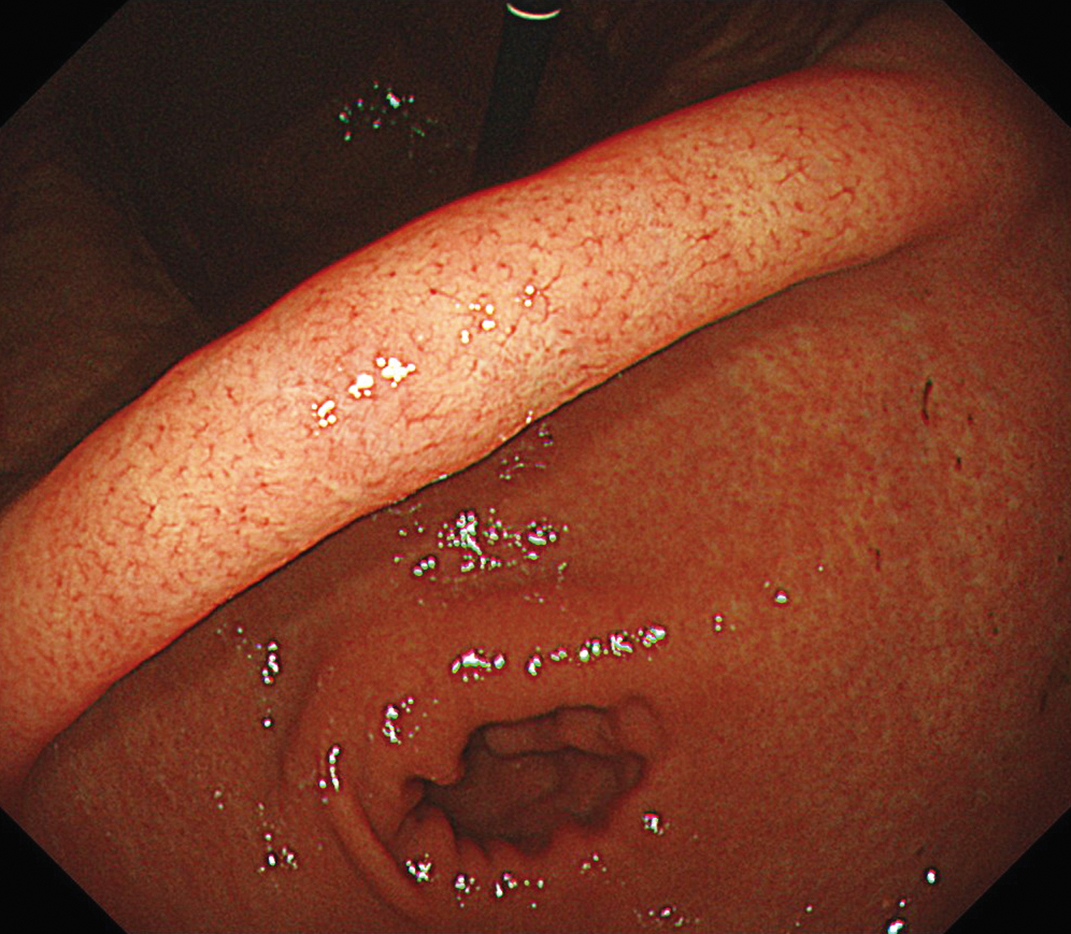

EVIS X1×GIF-1200N 症例画像

胃体部 見下ろし観察

1視野で体上部から胃角まで明るい視野での観察に貢献する